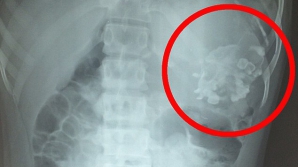

ÎNGROZITOR! Ce au scos medicii din abdomenul unui adolescent internat cu dureri de stomac (VIDEO)